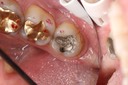

Alan Chinn #3 pre-op

Alan Chinn #3 caries removal 2

Alan Chinn #3 prep

Alan Chinn #3 finish